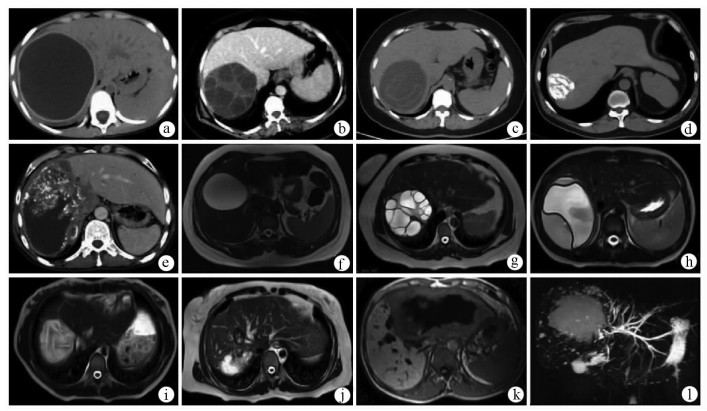

Expert consensus on the imaging diagnosis of hepatic echinococcosis

Radiology of Infection Sub-branch, Radiology Branch, Chinese Medical Association, Committee on Radiology of Infectious, Radiology Branch, Chinese Medical Doctor Association

2021, 37(4): 792-797. DOI: 10.3969/j.issn.1001-5256.2021.04.014

Abstract(1244) HTML (604) PDF (2065KB)(121)

Abstract:

Echinococcosis is a zoonotic disease with global distribution and has become an issue seriously affecting public health around the world. Imaging technology plays an important role in the early diagnosis, preoperative evaluation, and treatment outcome monitoring of hepatic echinococcosis. At present, no consensus has been reached on the imaging diagnosis of echinococcosis, which brings difficulties in the learning and training of imaging professionals and the standard diagnosis and treatment of echinococcosis in clinical practice. For this reason, Beijing YouAn Hospital, Capital Medical University, and The First Affiliated Hospital of Xinjiang Medical University organized the radiologists engaged in infection and inflammation from several hospitals to reach a consensus on the basis, principles, and criteria for the imaging diagnosis of echinococcosis and the differential diagnosis of echinococcosis, with reference to international guidelines, related articles, the latest research findings in China and globally, and the methodological requirements for the establishment of guidelines and standards in evidence-based medicine, so as to provide a clear diagnostic basis for clinicians in the clinical application of hepatic echinococcosis imaging.